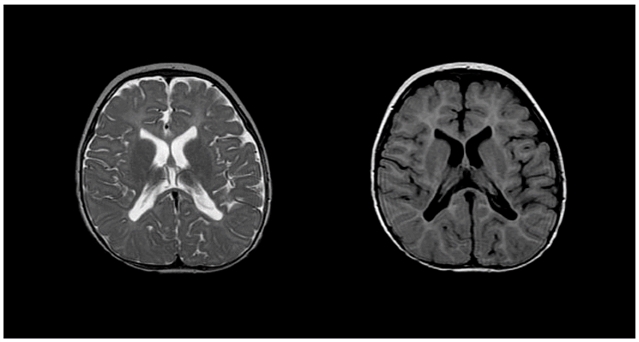

• MRI 特征:内囊、放射冠、视辐射区髓鞘缺失,T1 低信号、T2 弥漫高信号。

佩梅病患者的 T2(左)与 T1(右)MRI 图像显示内囊、近侧放射冠及视辐射区域髓鞘发育缺失。